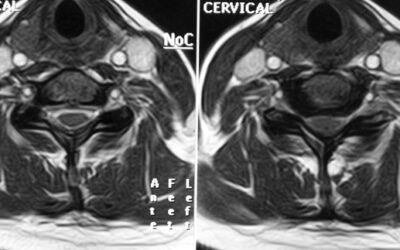

Mielopatía Cervical por Cervicoartrosis (MEC)

La mielopatía cervical por cervicoartrosis (o mielopatía espondilótica cervical) es la causa más común de disfunción de la médula espinal en adultos mayores. Se produce debido a cambios degenerativos relacionados con la edad en la columna cervical, que incluyen...